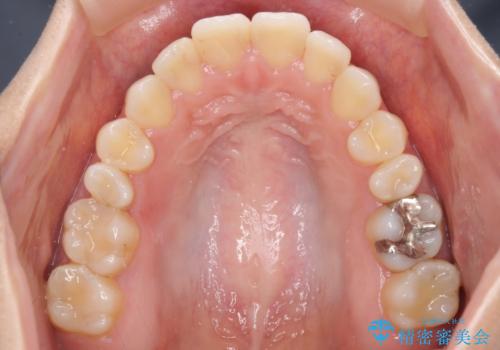

- オープンバイトのため、話しているときの見た目が気になるとのことで来院された患者様です。

下顎骨は左側にシフトしており、咬み合ったときには奥歯と前歯の一部しか接触していない状態でした。

骨格的な左右差は歯列矯正は改善できないため、上下歯列が全体的に接触することをゴールとしてインビザラインにて矯正治療を行うこととしました。

前歯のデコボコの解消と並行して上下の奥歯を圧下させるようにすることで、前歯を接触させるように計画しました。

上下の隙間に舌が入り込むことがオープンバイトの原因であったため、舌の筋肉のトレーニングも並行して行い、後戻りの抑制を図りました。